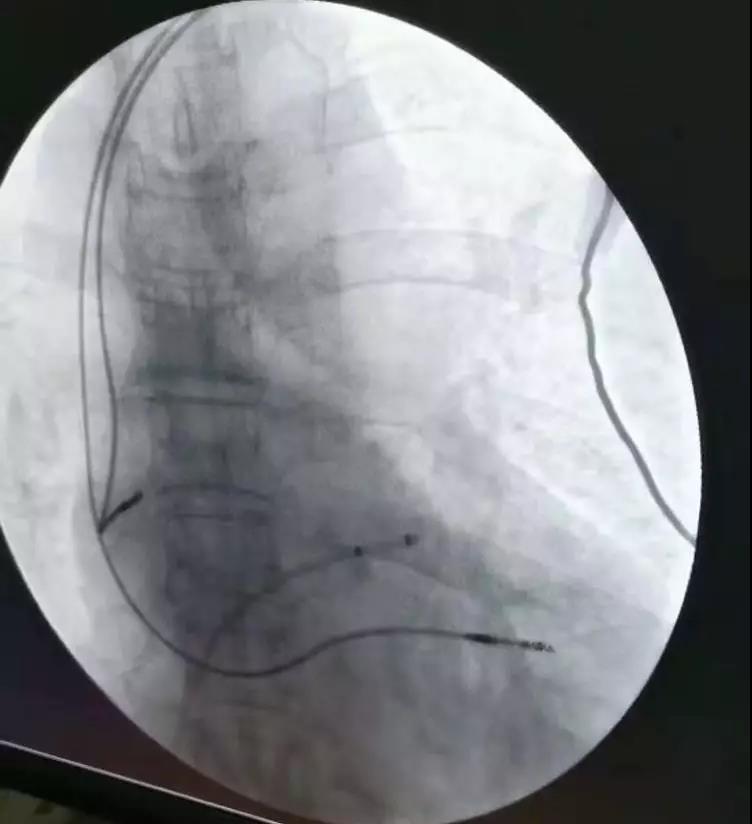

心内科一病区成功开展多例心脏起搏治疗

心脏起搏器植入术是指人工植入心脏起搏器,用特定频率的脉冲电流,经过导线和电极刺激心脏,代替心脏的起搏点带动心脏搏动的治疗方法,是治疗不可逆的心脏起搏传导功能障碍的安全有效方法,特别是治疗重症慢性心律失常。

临时起搏器的适应症如下

1、紧急的起搏功能:如患者出现心脏骤停、晕厥或阿-斯综合征,需紧急植入临时起搏器;

2、预防性的临时起搏功能:如外科手术中,部分患者心率特别慢,可植入临时起搏器,保证手术期间安全;

3、过渡性治疗:患者出现病态窦房结综合征或高度房室传导阻滞,在植入永久性起搏器之前,选择临时起搏器作为过渡治疗。